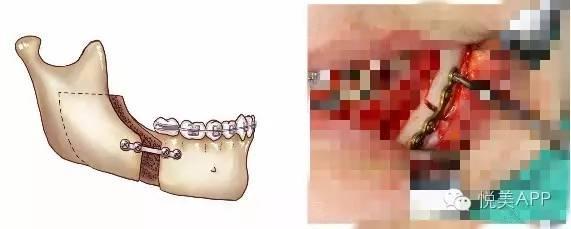

第二步:正颌外科手术,将长出来的部分骨头切除,然后往回推,固定住,形成正确咬合状态~

第一种:下颌骨矫正——将下颌骨截骨,去除一段,整体后退,固定,不但缩短下颌的长度,而且在后退的同时伴有上颌骨向上旋转,下颌角的角度变小,侧面也更好看,如果下巴颏太长,还可以缩短。

移动远心骨段之后~固定

固定

检查咬合并固定

第三步:恢复后进行,术后正畸,精细化调整咬合。

第四步:拆除牙套,开始终身佩戴保持器。